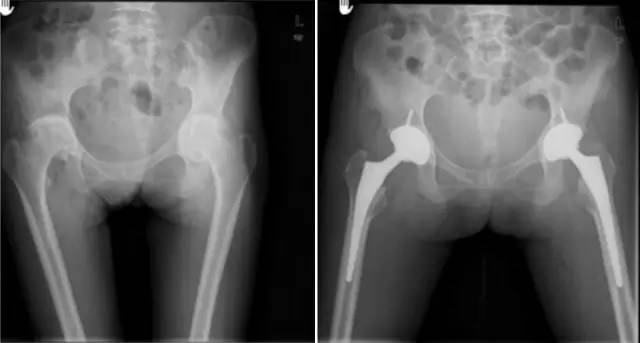

各种晚期骨关节病的关节置换手术治疗是北京清华长庚医院关节外科中心的一大特色,包括股骨头坏死、髋膝骨关节炎、类风湿关节炎、强直性脊柱炎、髋关节发育不良、关节强直、超过80岁的超高龄股骨颈骨折患者的关节置换手术等,我中心在人工关节初次置换及翻修上作了大量工作,置换的难度和手术效果方面已达到国际先进水平,导航下全膝关节置换术:大大提高膝关节置换手术的精确度。

股骨头缺血性坏死

髋关节发育不良

强直性脊柱炎双髋强直

股骨颈骨折